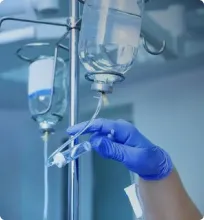

Помимо обязательной медикаментозной поддержки, в стационаре нашего наркологическая помощьа параноикам оказывают психотерапевтическую, психологическую помощь. Психотерапевты проводят сеансы когнитивно-поведенческой и семейной терапии, показывающие высокую эффективность в лечении расстройства психики.